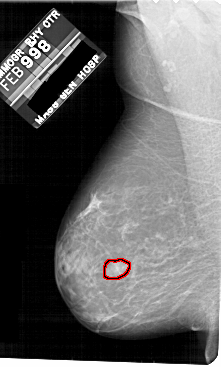

A_1811_1.LEFT_MLO

FILE: A_1811_1.LEFT_MLO.OVERLAY

TOTAL_ABNORMALITIES 1

ABNORMALITY 1

LESION_TYPE MASS SHAPE IRREGULAR MARGINS MICROLOBULATED

ASSESSMENT 4

SUBTLETY 2

PATHOLOGY BENIGN

TOTAL_OUTLINES 1

BOUNDARY